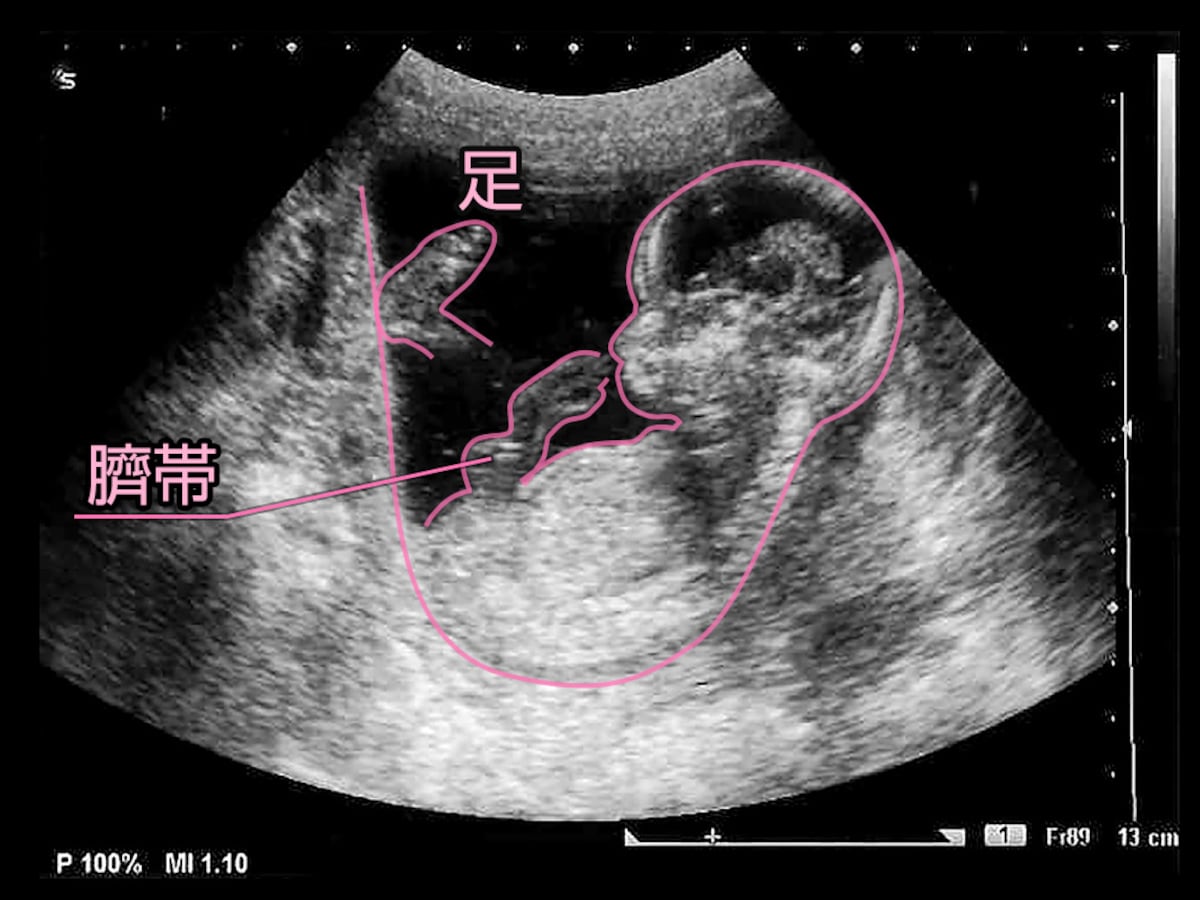

妊娠14週 3 6日 のエコー写真 体験談

胎児エコー動画 妊娠14週1日 Ultrasound In Japan Youtube

妊娠14週 赤ちゃんのエコー写真 超音波写真まとめ たまひよ

妊娠14週1日 14w1d の超音波 エコー 写真

妊娠14週 赤ちゃんのエコー写真 超音波写真まとめ たまひよ

妊娠14週 赤ちゃんのエコー写真 超音波写真まとめ たまひよ

第1子妊娠記録 妊婦健診 妊娠14週 14w 4dエコー 4ヵ月 Youtube

育児日記 新米パパの記録 妊娠14週目の超音波写真

妊娠14週 赤ちゃんのエコー写真 超音波写真まとめ たまひよ

妊娠14週目 14w0d 6d のエコー写真とエピソード 妊娠4ヶ月 Cozre コズレ 子育てマガジン

妊娠14週 赤ちゃんのエコー写真 超音波写真まとめ たまひよ